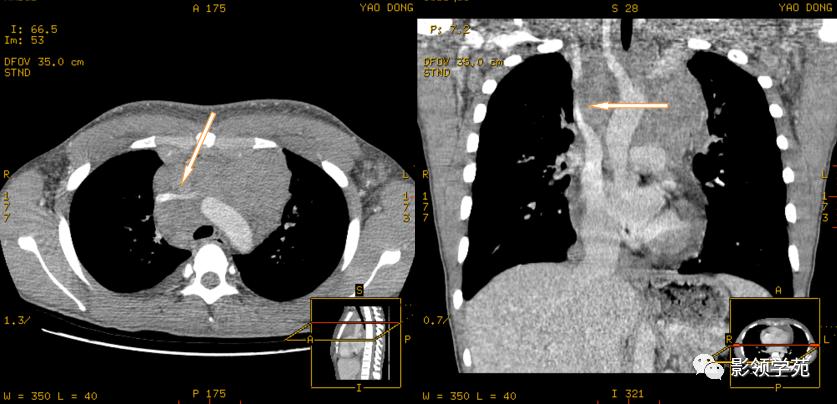

CT特征:

1、多数病灶与颈部甲状腺相延续,多位于气管前间隙,亦可伸入到气管及食道后方,冠状位及矢状位重建有利于显示连续关系。

2、肿块边缘较光滑,密度多不均匀,可见单发或多发低密度区,钙化较常见。

3、平扫CT值较高,增强后强化明显,且延迟较长时间。

4、多数病例纵隔内大血管及气管有推移表现。

矢状位重建显示更清晰